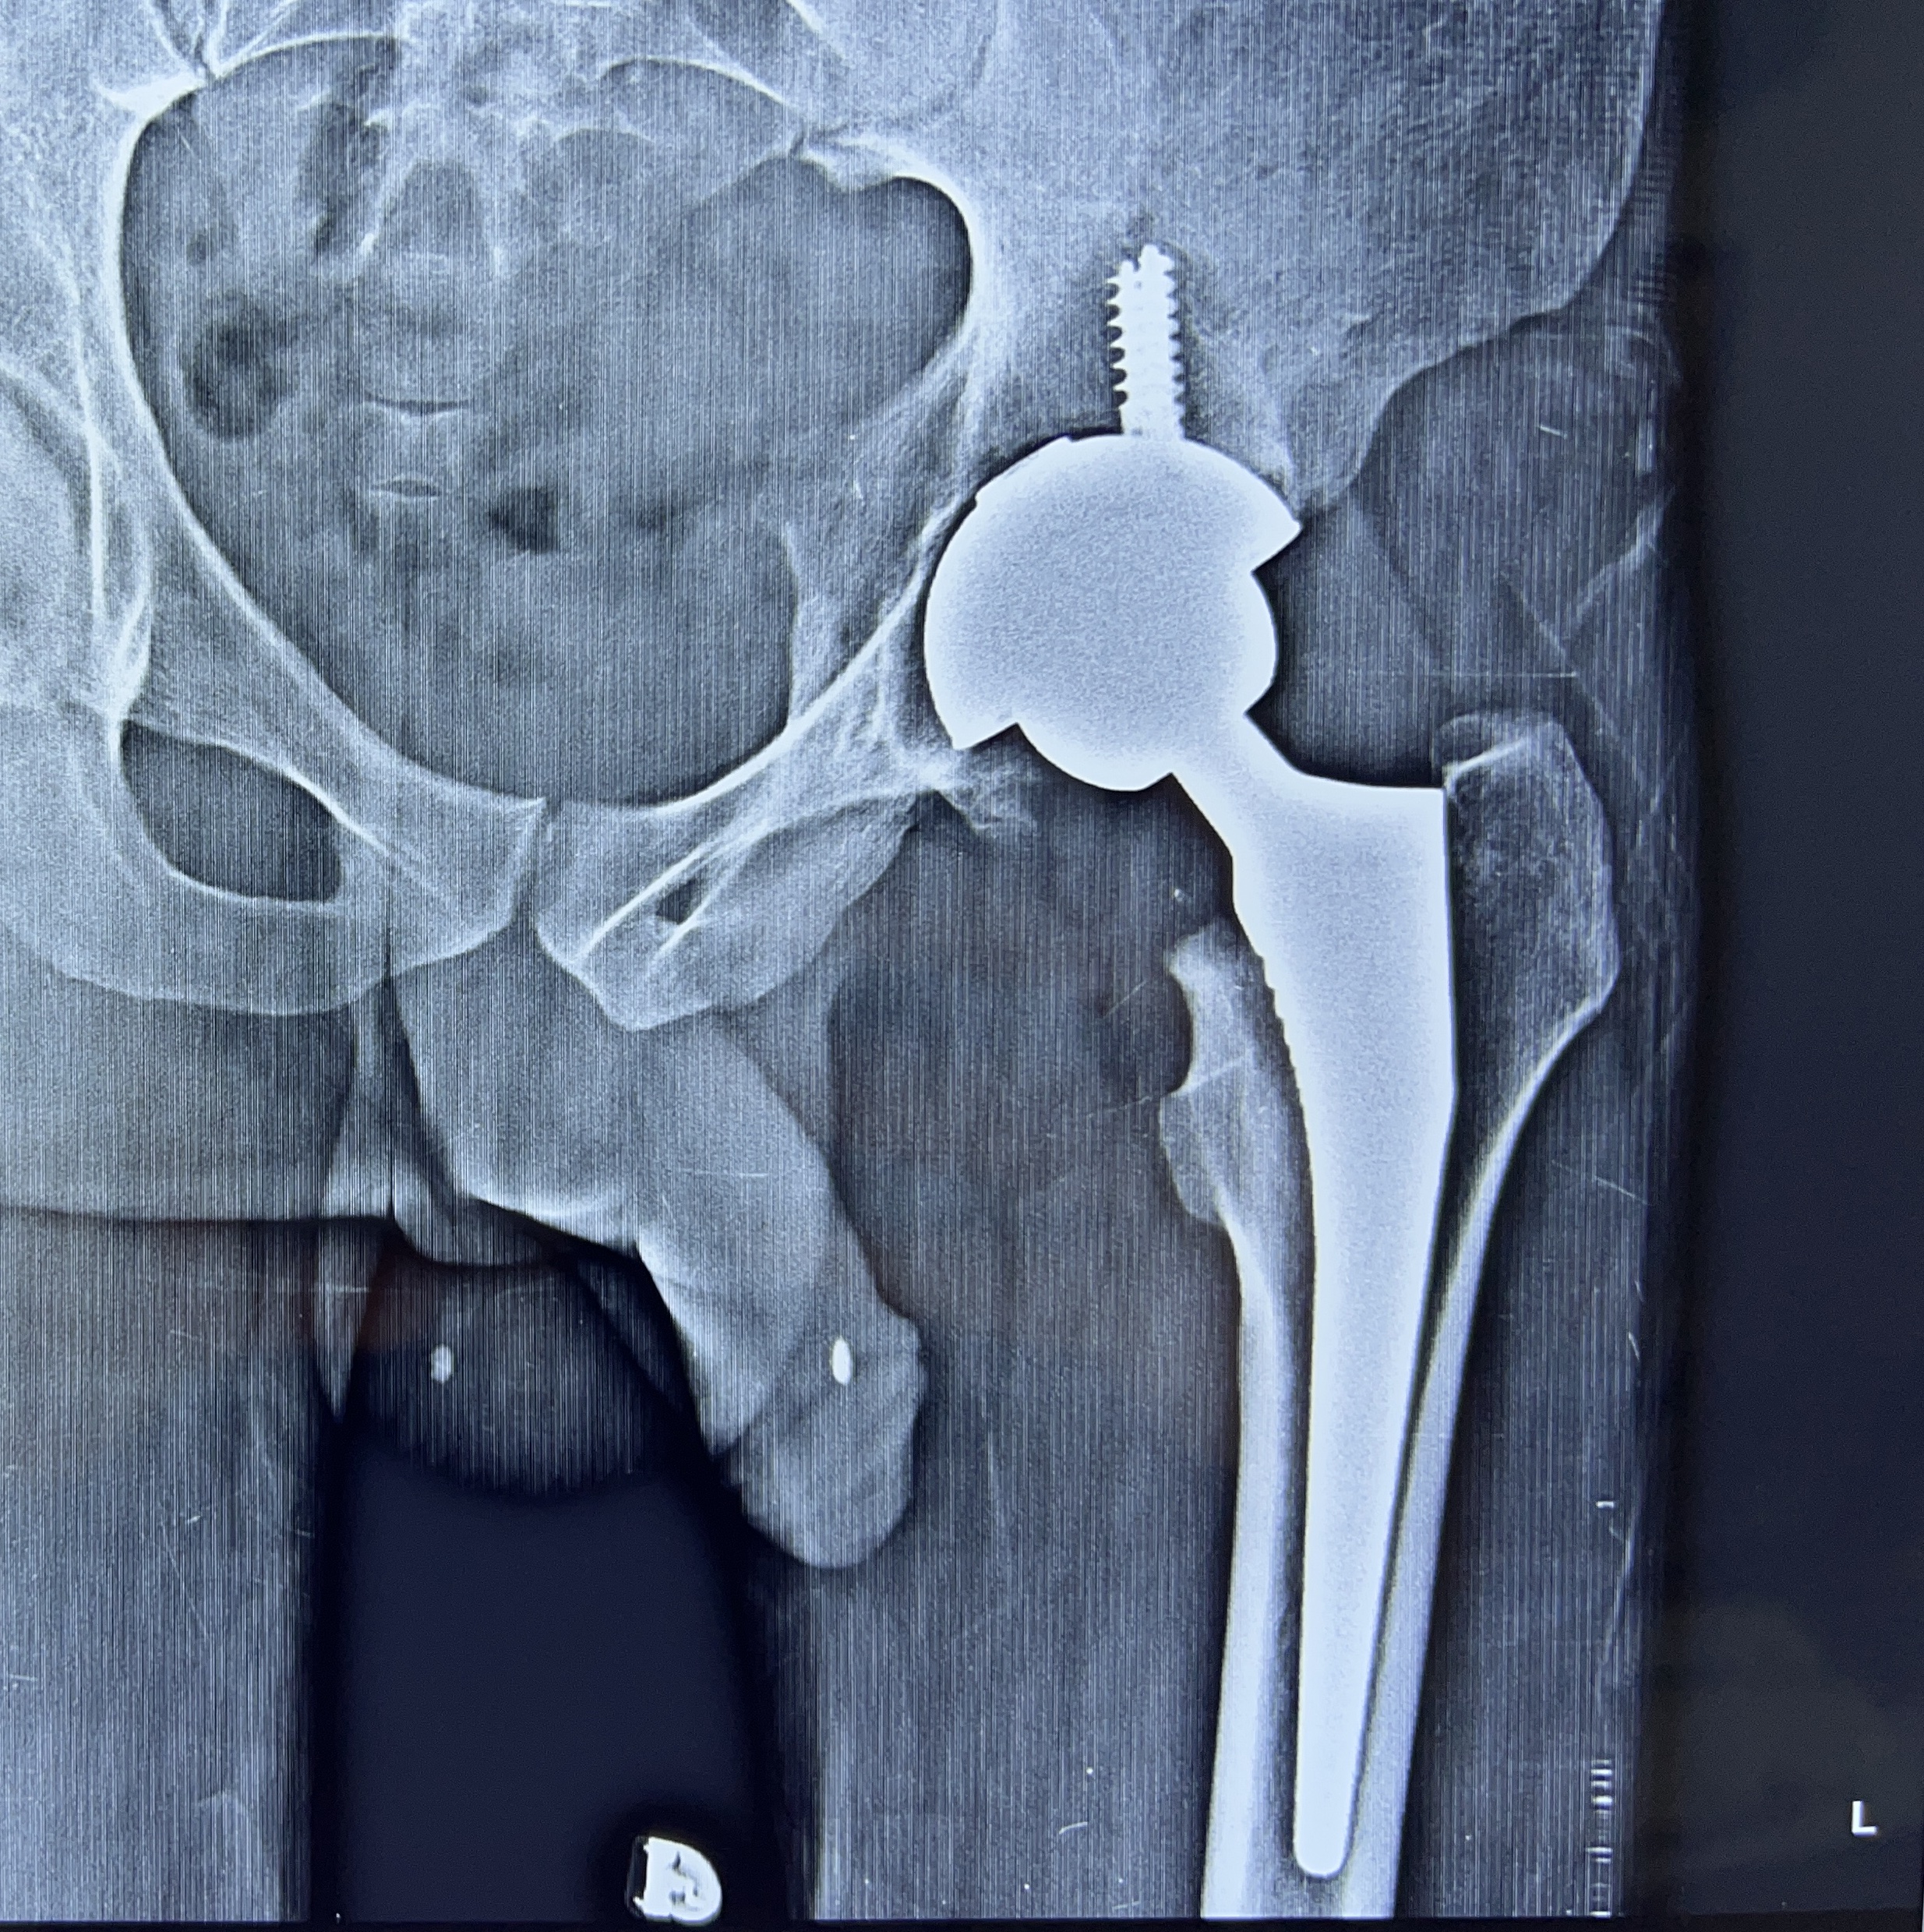

Total Hip replacement surgery is a surgery in which the worn out or damaged surface of the hip joint is replaced with prosthetic artificial surface made up of special metals like ceramic, chromium-cobalt, oxinium, titanium or polyethylene. The aim of this surgical procedure is to relieve you of your pain, deformity and swelling. So that you can get back to your active life. Now, that you have been suggested surgery, we help you plan and go for it.

Robotic hip replacement surgery is performed by the surgeon with the help of the robot. The surgeon will open up the hip, make a real time map of the deformed/ damaged surface ends of the bones and then using the robot, plan the surgery. Once the surgery is virtually performed on the robotic screen, the robotic burrs are used to burr off/ shave off the surface and tissue balance is achieved throughout the range of movement, an artificial implant is fitted on the surface. The wound is closed and dressing applied. You are then shifted to the recovery room!